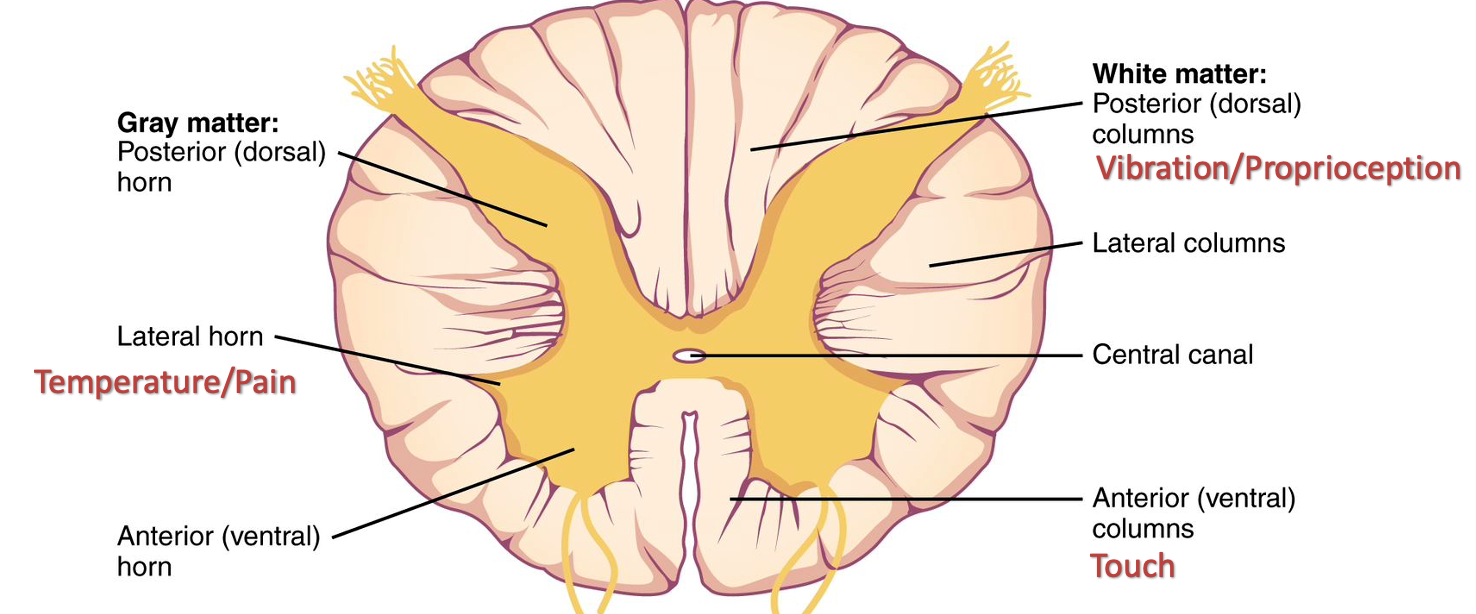

5) Sensory / Proprioception

Spinothalamic Tract

- Pain and Temperature

- Crude touch (Light Touch without localization)

- Fibers cross & pass upward into thalamus

Posterior Columns

- Position and vibration

- Fine touch

- Synapse in medulla, cross & continue on to thalamus

Other Notes

Spinal thalamic track

- Posterior Column; Vibration/Proprioception

- Anterior (ventral) Column; Touch

- Lateral Horn; Temprature/Pain

Brown squart syndrome

Lesion results in:

Dorsal column lesion – Ipsilateral loss of light touch, vibration, and position sense Lateral corticospinal tract lesion – Ipsilateral upper motor neurons signs Lateral spinothalamic tract lesion – Contralateral loss of pain and temperature sense